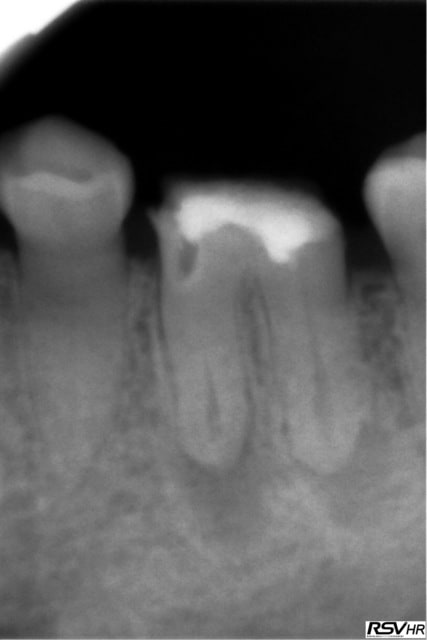

Voici un exemple de couplage microscope opératoire/cbct

RTE 36 en octobre2012 ;3 heures de RTE pour recherche de canaux sous micro inserts ultrasons/il y avait une LIPOE

digue+hypo+système R-endo microméga instruments à mains

vérification au CBCT en 2016

disparition des LIPOE

ici on obtient une guérison apicale

Tu peux me faire un CBCT de 35 ? Il semble y avoir un 4ième bien que le tt endo soit correct.

Je viens de faire une bio sur 45 (pulpite). Et je crois que j'ai ma petite idée sur la cause du 4 ième de 35. -)